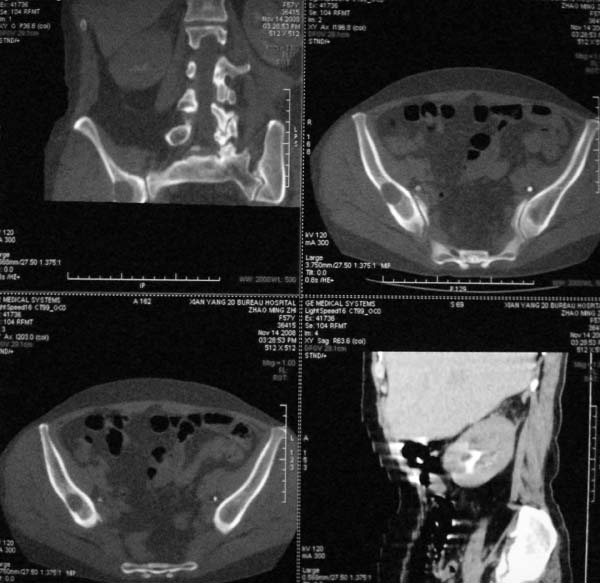

以下是引用dr.yang在2008-11-9 21:56:00的发言:[br]右肾上极占位?建议增强

以下是引用x-man在2008-11-9 22:30:00的发言:[br]建议先增强,右肾影明显增大,上极见边不清低密度肿块影,肿瘤待定.

以下是引用卜一在2008-11-10 8:09:00的发言:[br]建议先增强,右肾影明显增大,上极见边不清低密度肿块影,肿瘤待定.支持!另:第一次碎石是否肾受到损伤?合并感染?不知第一次碎石前是否做过彩超?

以下是引用dsl555在2008-11-9 23:57:00的发言:[br]建议先增强,右肾影明显增大,上极见边不清低密度肿块影,肿瘤待定. [br] [br]